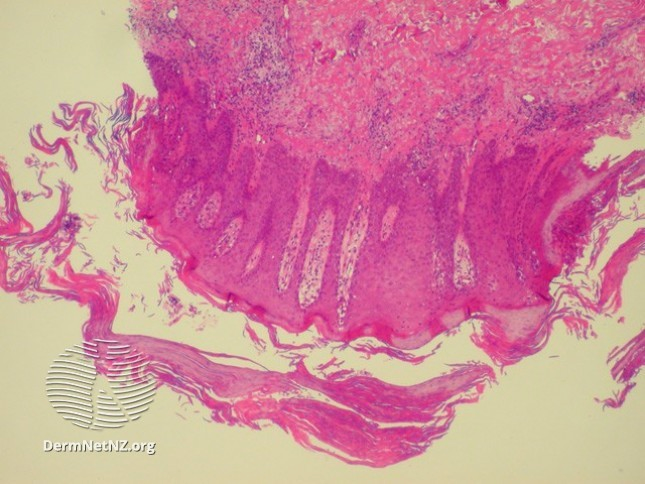

Q: Ever notice how psoriasis doesn't really get impetiginized/superinfected but eczema does? Why do you think that is?